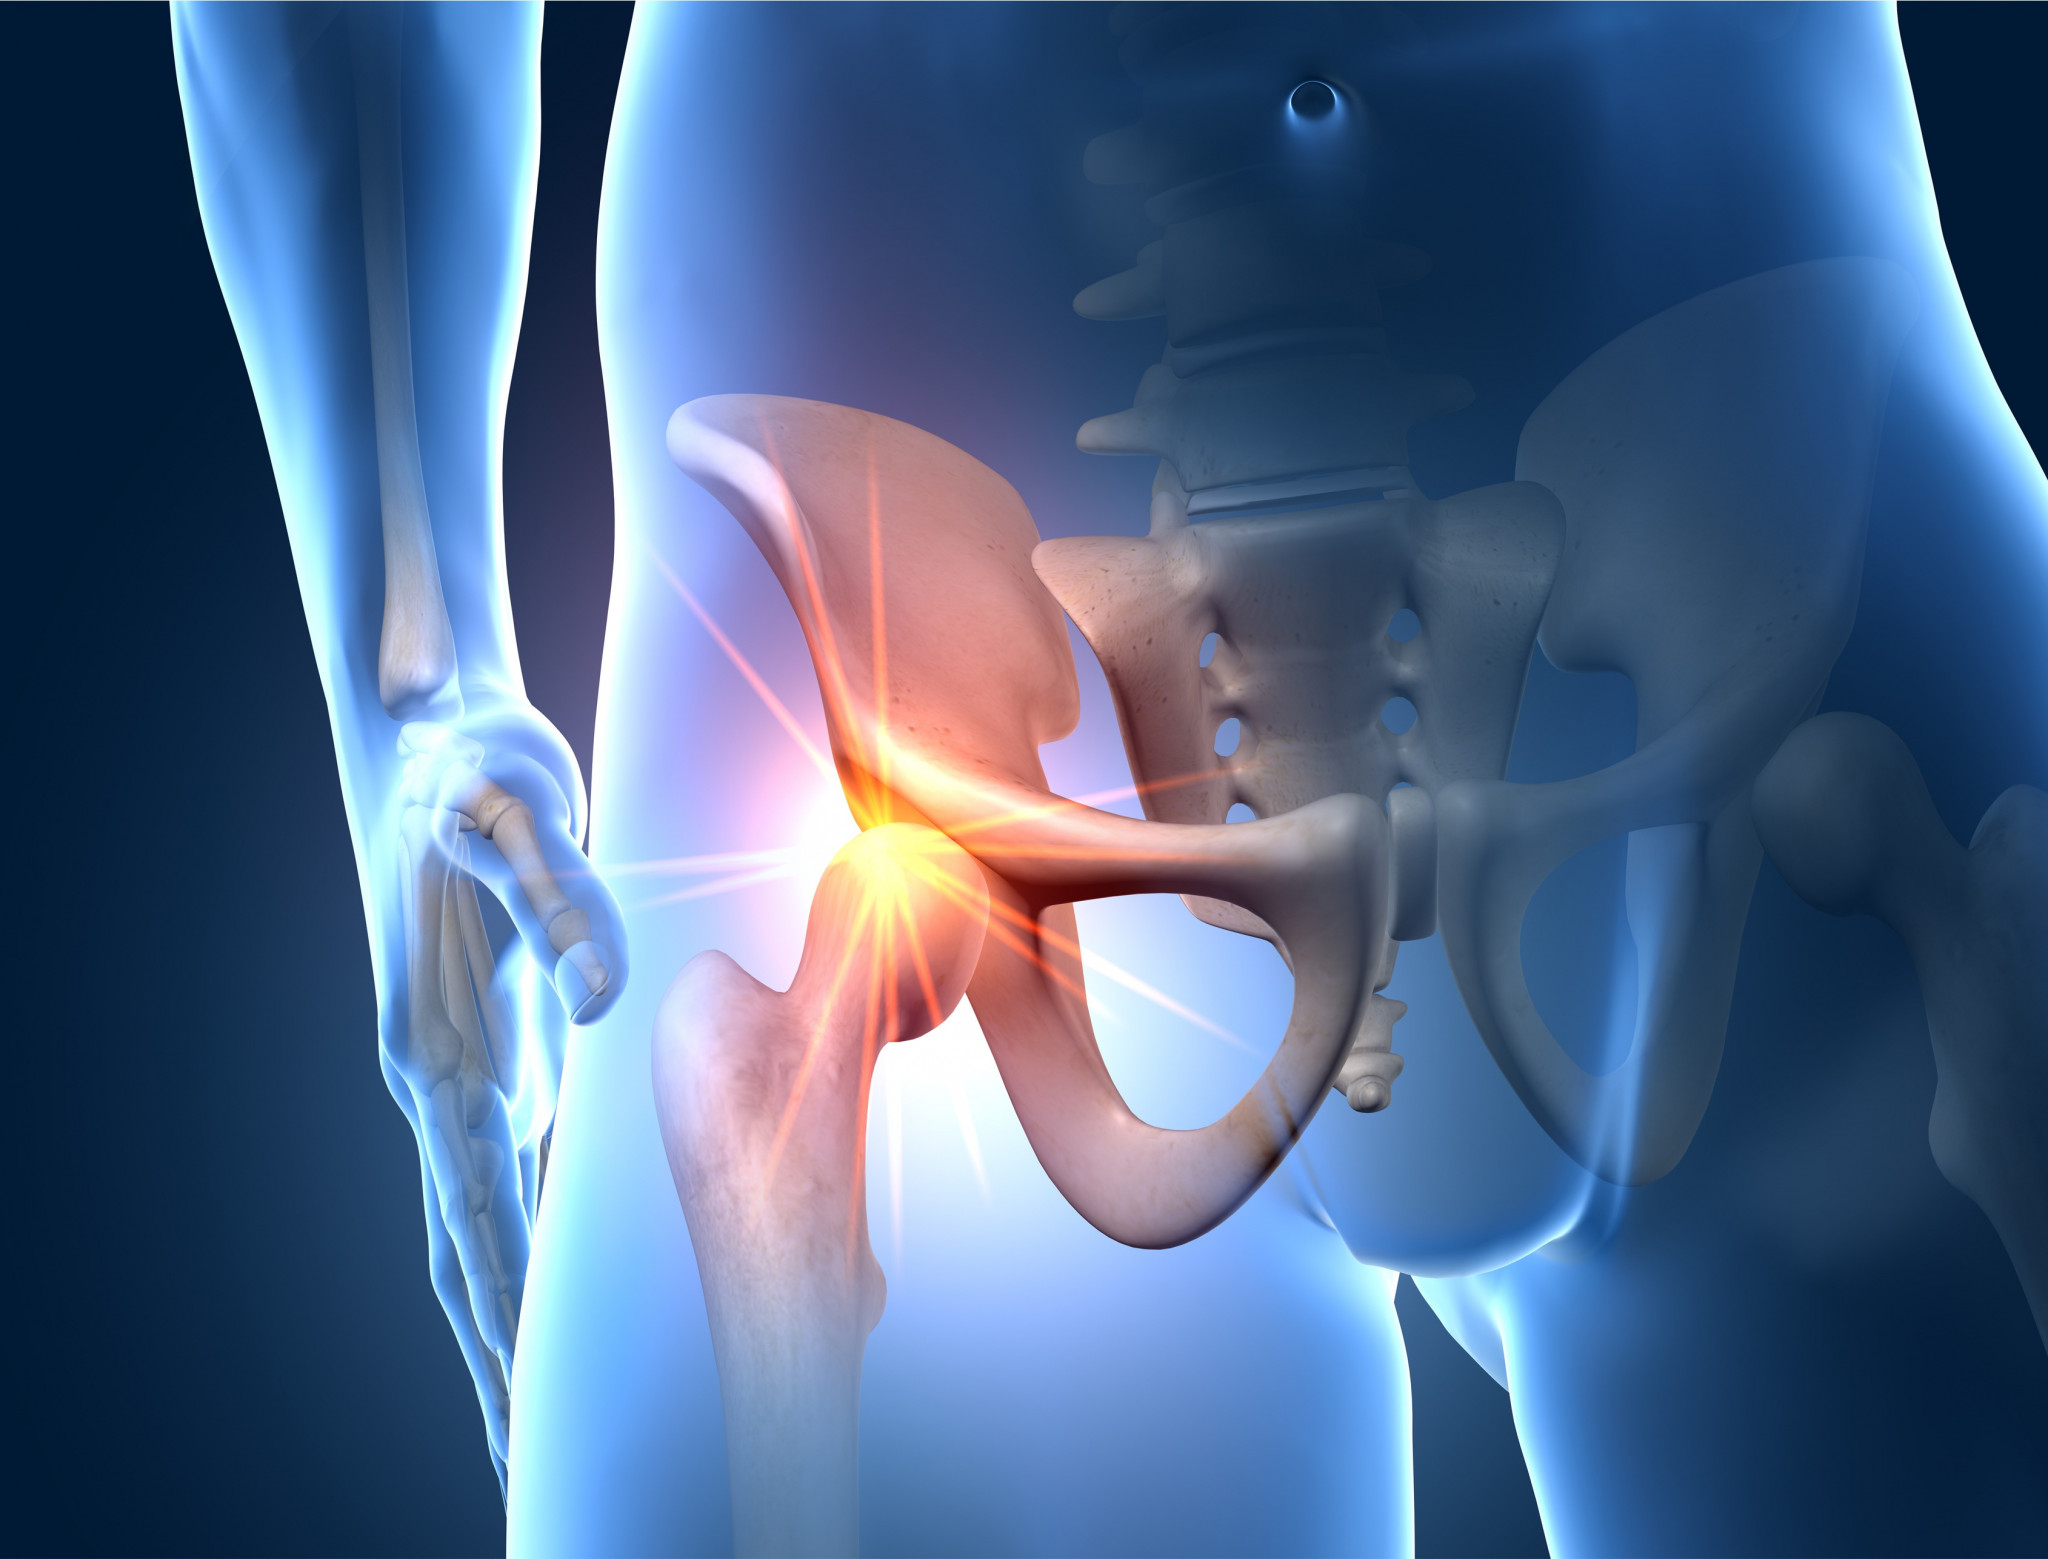

Unsere Fachklinik ist ein Kompetenzzentrum für Primär- und Revisionsendoprothetik. Hüftarthrose, also die Abnutzung des Hüftgelenks, führt oft zu starken Schmerzen und eingeschränkter Beweglichkeit, sodass ein Funktionsverlust und die Einschränkung der Gehfähigkeit die Folge sind.

Neben altersbedingter Abnutzung sind häufige Ursachen der Arthrose auch Entzündungen (Rheuma), Unfälle oder angeborene Veränderungen, die zur Zerstörung des Hüftgelenkes und der Implantation einer Endoprothese führen.